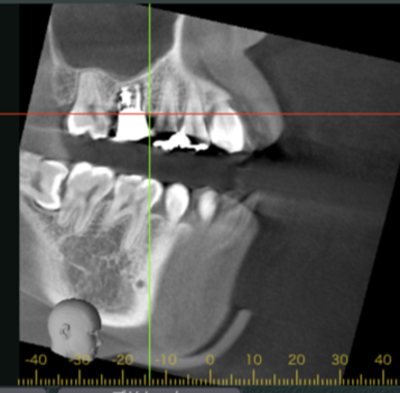

初診時CT画像

初診時デンタルX線写真とCT画像。

根管外に不透過像とそれを取り囲む透過像を認める。

コアを除去すると、分岐部へつながるパーフォレーションを認めた。

これが排膿の原因であったため、保存は困難と判断した。